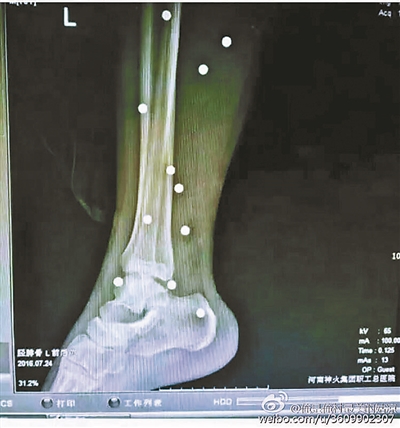

傷者體內(nèi)取出的鋼珠

爆炸導(dǎo)致鋼珠遍布傷者身體各處

黃明的伯伯對(duì)北青報(bào)記者表示,由于黃明直接踩到了爆炸物,所以傷情最為嚴(yán)重,“他的腿被炸斷,身體內(nèi)被炸進(jìn)了40多顆鋼珠。手術(shù)后已經(jīng)從體內(nèi)取出29顆鋼珠,還有十多顆鋼珠沒(méi)有取出來(lái)?!备鶕?jù)黃明的入院記錄,他全身有多處爆炸傷,且全身多處異物存留。

爆炸發(fā)生時(shí),陳浩的位置與黃明靠得很近,因此也受傷較重。他告訴北青報(bào)記者,經(jīng)過(guò)10多個(gè)小時(shí)的手術(shù)后,醫(yī)生從他身體里取出了12顆鋼珠。目前,他和黃明兩人經(jīng)過(guò)手術(shù)后,已從重癥監(jiān)護(hù)室轉(zhuǎn)至普通病房。其余三人中,陳剛的臀部受傷,當(dāng)天晚上在醫(yī)院清理完傷口后便回了家,而同行的兩名女生身上有一些擦傷。